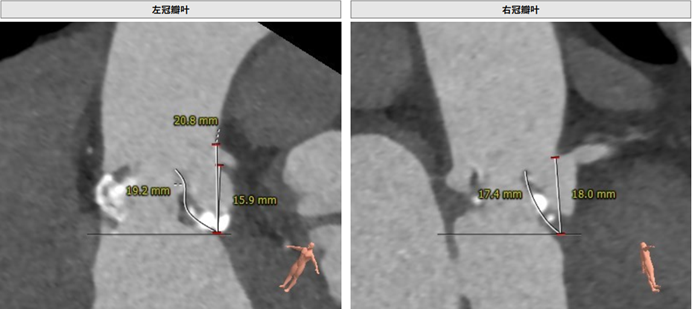

左冠瓣叶长度:19.2 mm,右冠瓣叶长度:17.4 mm

由于患者瓣叶增厚且稍长,法式窦结构偏小,术者团队认为术中可能存在发生双侧冠脉阻塞的风险。结合患者主动脉根部情况及病情等综合因素,吴连拼院长在组织科室集体对患者病变进行深入分析和多次讨论后决定通过球囊预扩后予以进一步确认,必要时行冠脉保护。选用22 mm球囊预扩张。